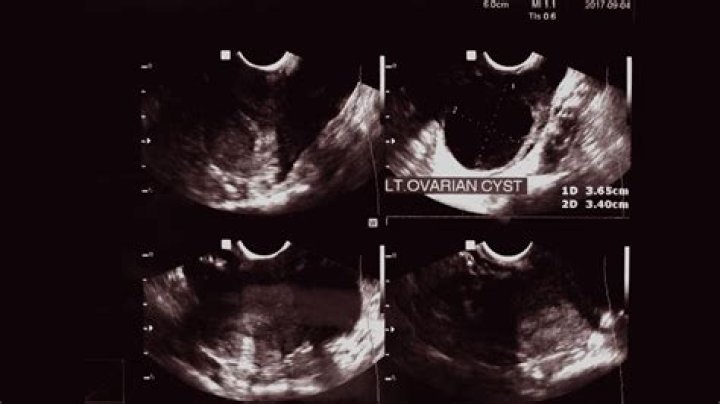

Do ovarian cysts smell when they rupture?